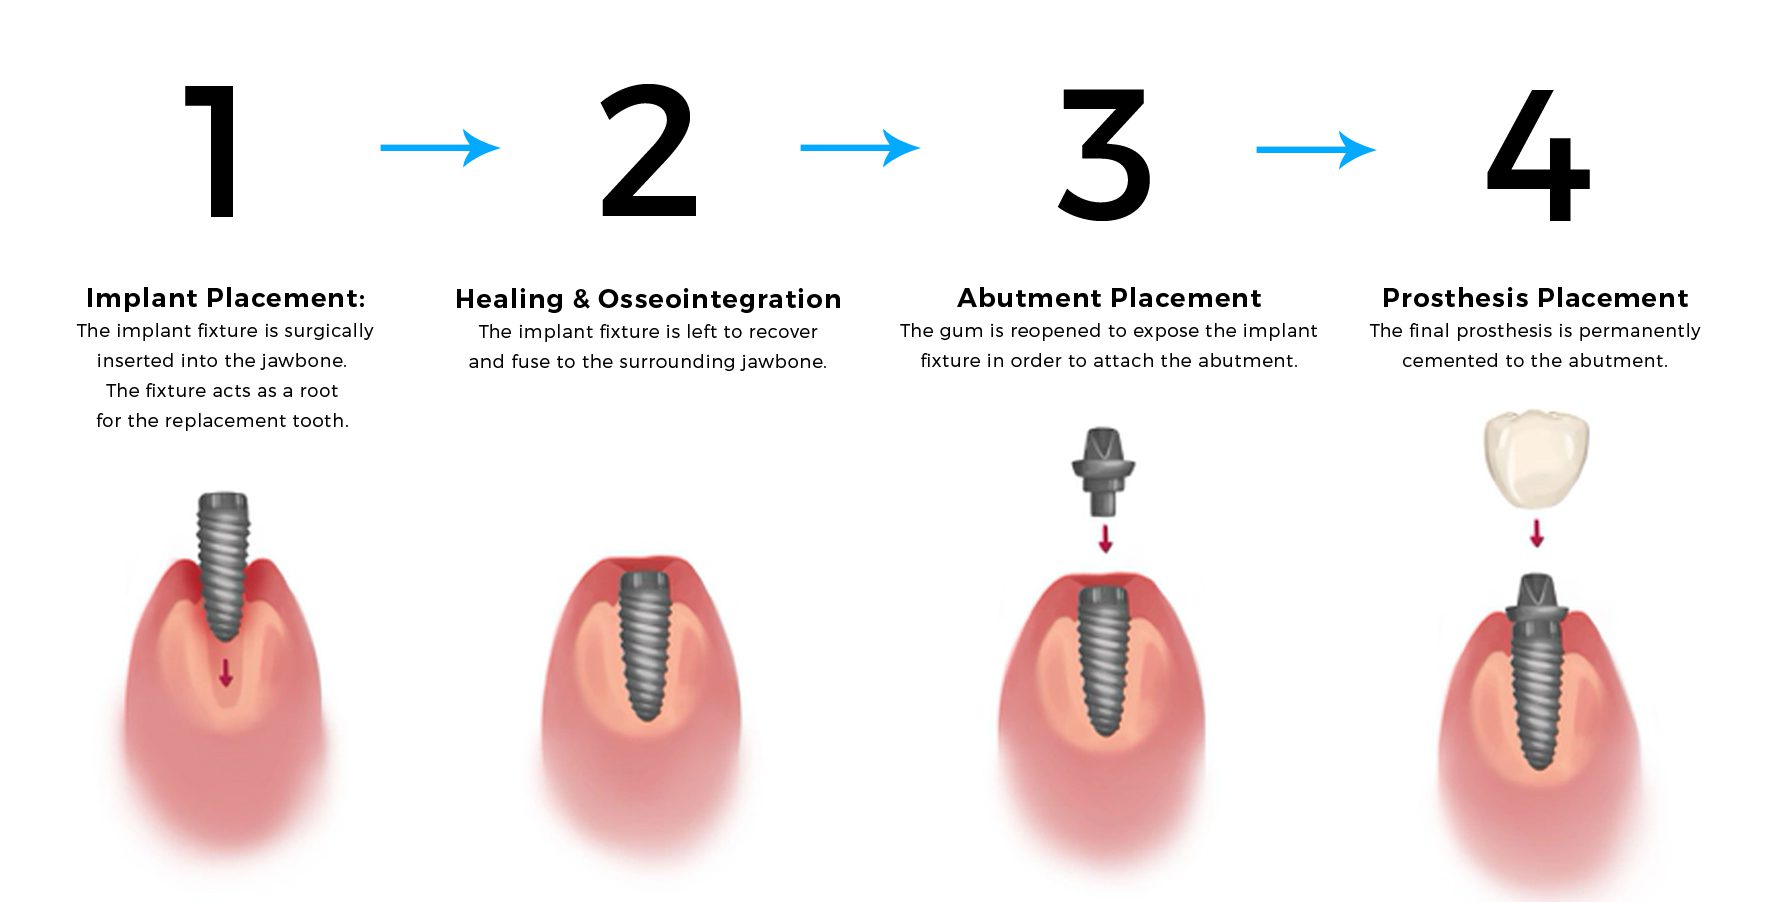

Core Stages of Implant Surgery

The entire dental implanting process can generally be broken down into four core stages, spanning over the course of 4 – 6 months in total. The four stages are; implant fixture placement, healing & osseointegration, abutment placement and the placement of the final dental prosthesis.

For the majority of patients, these 4 core stages are not carried out in a single dental visit or surgery. The recovery time of 4 – 6 months post-surgery allows the implant fixtures to heal and permanently fuse with the surrounding jaw bone (Stage 2: Osseointegration).

The long term success of any dental implant is highly reliant on the osseointegration of the implant with the surrounding bone. Failure to osseointegrate will result in the failure of the dental implant.

Once the dental implant fixture has adequately osseointegrated with the jaw bone, the abutment and prosthesis can be attached to the implant fixture, completing the entire dental implant process.

1. Implant Placement

The implant fixture is surgically inserted into the jawbone. The fixture acts as a root for the replacement tooth.

2. Osseointegration

The implant fixture is left to recover and fuse to the surrounding jawbone.

3. Affix Abutment

The gum is reopened to expose the implant fixture in order to attach the abutment.

4. Prosthesis Placement

The final prosthesis is permanently cemented to the abutment.